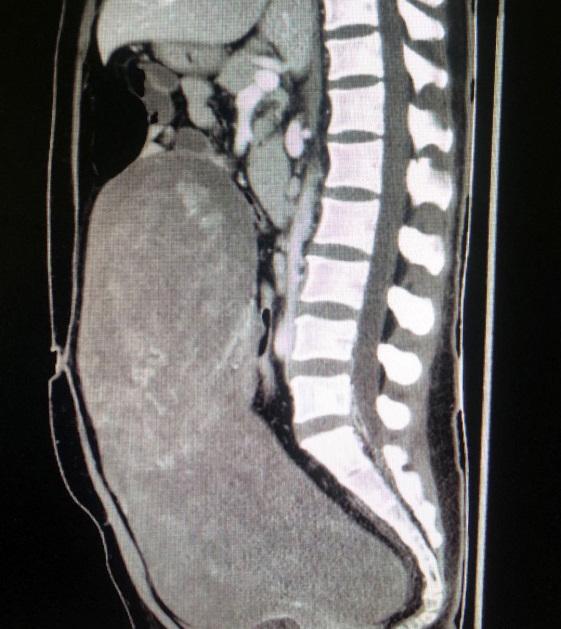

去年11月开始,42岁的张女士突感腹部胀痛难忍,肚子日渐肿胀,腹围增大。2周后,于当地医院就诊,经检查显示,张女士的腹腔内有一巨大肿物,医生建议张女士尽快转诊上级医院进行手术治疗,否则将有生命危险。了解到北京友谊医院肿瘤救治的综合实力后,张女士在家人的陪同下慕名前来就诊。经诊断,张女士盆腹腔瘤体巨大,上界达膈下,向下充满盆腹腔,侵袭范围如此之大的盆腔肿物非常罕见。为了能准确评估肿瘤来源,血供、侵及范围,以便后续手术治疗,需要对张女士进行增强影像学检查。但因患者本身患有输尿管、肾结石,加上肿瘤压迫,导致肾功能不全,处于肾衰竭边缘,如若进行增强影像学检查会有急性肾衰竭的危险。

针对张女士的情况,妇产科组织全院专家会诊。多科室专家讨论后认为,她的盆腹腔巨大肿瘤不除外子宫血管平滑肌瘤或卵巢巨大肿瘤可能,若没有增强影像学检查评估,后续手术风险极大。因此,决定先行双侧输尿管支架置入术,缓解其尿路梗阻;监测她的肾功能情况,待有所好转后,再行增强CT检查及三维血管重建,并进行肿瘤切除手术治疗。

12月10日,泌尿科医师宁晨为张女士成功放置双侧输尿管支架,引流出脓性尿液。经抗感染治疗,张女士血肌酐轻微下降。在影像科大力协助下进行了增强CT检查及三维血管重建。

12月18日上午,经过了充分的术前准备,手术正式开始。麻醉科主任医师柯敬东担任主麻医师,手术由妇产科郝增平主任主持,主任医师金影、主治医师金华共同操刀手术。手术团队在开腹探查后发现患者盆腹腔巨大肿瘤长径40cm,来自左侧子宫阔韧带,压迫周围组织呈膨胀性生长,达上腹腔,瘤体表面血运丰富,并与肠管及周围组织粘连。郝增平主任有着妇科大型疑难手术丰富的经验,在金影主任医师的默契配合下,一步一步小心的分离粘连并牢靠止血,经细致谨慎的操作,该手术历时2个小时终于顺利完成,术中出血仅100ml。该瘤体体积40cm×31cm×20cm,重达13斤,术后诊断为子宫阔韧带粘液样及脂肪平滑肌瘤。张女士术后恢复良好,7天后康复出院。手术后肾功能逐渐恢复正常,于当地医院定期随访。